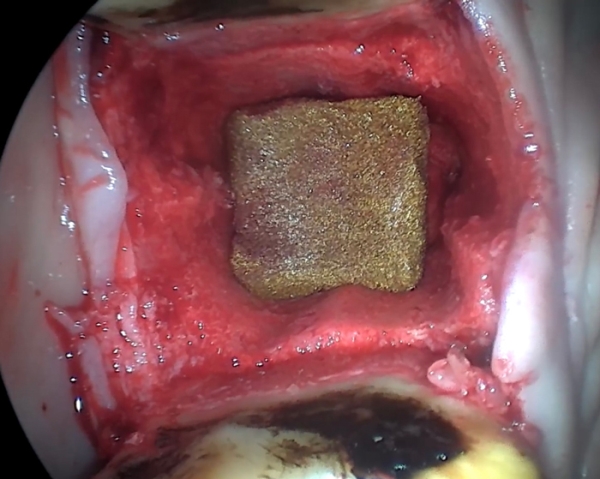

Kun Airgid-sieni on asetettu paikalleen, se voi imeä enemmän kuin oman painonsa verran verta, mikä vähentää haavan ”tyhjää tilaa” ja vakauttaa verihyytymän. Tämä on ensimmäinen askel kohti hemostaasia. Primaarinen verenvuoto tyrehtyy, kun Airgid asettuu mukavasti hampaankoloon.

Kun hammas on irrotettu ja irrotuskohta on täynnä verta, haavaan levitetään kuivaa Airgidiä. Airgid voidaan leikata halutun kokoisiksi palasiksi, mutta sitä ei saa puristaa.

Sieni täyttyy verellä ja edistää välittömästi verihyytymän muodostumista ja verenvuodon tyrehtymistä. Lisähuuhtelua ei tarvita, sillä Airgidin hoitaa hammaskuoppaa. Tarvittaessa haava voidaan ommella kiinni Airgidin ollessa paikallaan.